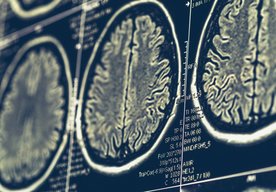

Vedec navrhuje plán, ako uniknúť z našej simulácie